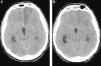

(A) TAC sin contraste a las 24 horas postembolización del aneurisma. Hipodensidad cortico-subcortical en territorio de ACA izquierda consecuencia de la complicación embolígena. (B) TAC sin contraste preangioplastia para tratamiento del vasoespasmo cerebral en el día 12° de HSA. Desaparición de la hipodensidad en territorio tributario de ACA izquierda (fogging effect).

Presentamos el caso de un varón de 51 años, fumador y con antecedente de hipertensión arterial, que sufre episodio brusco de bajo nivel de consciencia con puntuación de 6 en la escala de coma de Glasgow. En la tomografía axial computarizada (TAC), se objetiva HSA de predominio en cisternas de la base, cisura interhemisférica y datos de hidrocefalia aguda. La arteriografía cerebral muestra lesión aneurismática del complejo comunicante anterior, consiguiéndose cierre endovascular del saco aneurismático. Como incidencia en la comprobación final, se observa defecto de repleción en el origen de la arteria cerebral anterior (ACA) izquierda, en relación con suelta de trombo desde el cuello del aneurisma. Los intentos de repermeabilización resultan fallidos, con resultado de oclusión. La TAC a las 24h posprocedimiento evidencia hipodensidad córtico-subcortical compatible con infarto isquémico agudo en dicho territorio (fig. 1).

El paciente evoluciona con criterios sonográficos de vasoespasmo cerebral, alcanzando velocidades medias de 242cm/s el día 12.° del sangrado. La TAC, previa arteriografía para angioplastia cerebral, muestra desaparición de la hipodensidad frontal izquierda. Con el hallazgo de vasoespasmo angiográfico moderado de arteria cerebral media (ACM) izquierda, grave en ACM derecha, y vasoespasmo segmentario moderado de ambas arterias cerebrales anteriores (ACA), se realiza angioplastia con balón en ambos segmentos M1, con buen resultado. El estudio radiológico vuelve a mostrar a las 8 semanas de evolución, una lesión isquémica establecida en territorio tributario de la ACA izquierda.